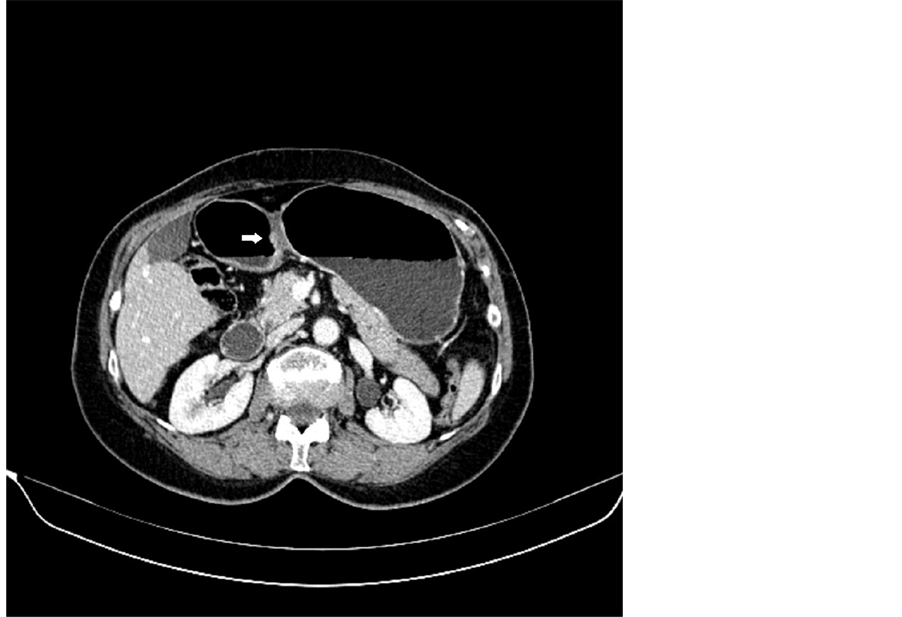

Figure 1. MDCT image in axial plane-T1a tumor.

CT staged as follows, 2 T1b and 1 T1a (3 EGC, 20%); 8 T3, 1 T4a and 3 T4b (12 AGC, 80%). Weighted Cohen’s kappa value showed almost perfect agreement between the two independent observers (weighted kappa = 0.8193) for this parameter. Pathological staging confirmed 12 out of 15 cases, with an overall accuracy of 80% for T staging. The 3 non congruent cases were all overstaged: 2 T1 overstaged at CT as T3 and 1 T3 overstaged as T4a (Table 2). No patient was understaged. Results of CT diagnostic performance for every stage of T are shown in Table 3.

Among patients with overstaged EGC, one had Small Mucosal type, according to Kodama’s classification, and one was type Pen A. At CT scans, the first showed an irregular thickening (approximately 12 mm) of the gastrojejunal anastomosis (stump cancer), extended for about 3 cm, with a single-layer pattern; the patient with Pen A EGC showed a three-layer pattern, in the presence of a polypoid tumor of the gastric antrum measuring 28 × 22 mm, with patchy contrast enhancement. Both cases showed a clean and smooth outer margin. Correctly staged EGC showed a modest thickening (7 - 14 mm), about 1.5 - 2 cm in size, with marked enhancement of the inner mucosal layer. In all three correctly staged EGC cases, three-layered pattern was visible.